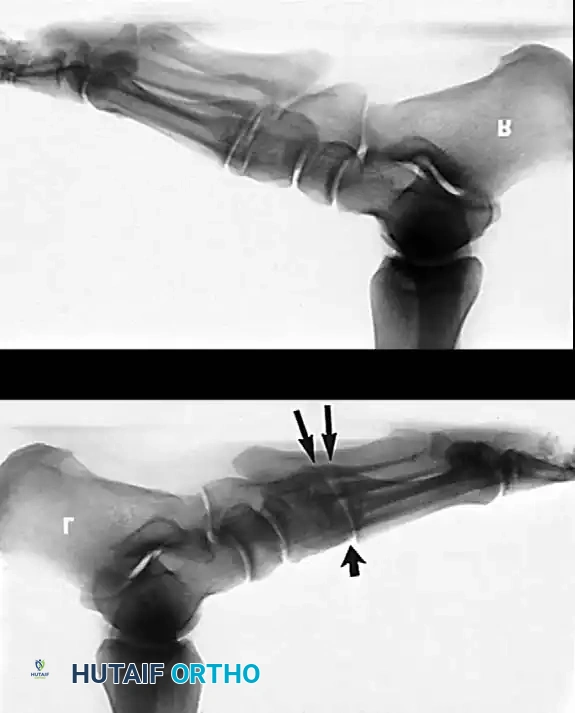

- Radiography: Degenerative arthritic changes are visible in the subtalar and/or talonavicular joints.

The gold standard for rigid Stage III PTTI. It involves the fusion of the subtalar, talonavicular, and calcaneocuboid joints.

* Correction: The deformity is corrected by manipulating the joints. The hindfoot must be fused in 0 to 5 degrees of valgus. Never fuse the hindfoot in varus.

* Fixation: Large cannulated screws are used for the subtalar joint (calcaneus to talus). The talonavicular and calcaneocuboid joints are fixed with screws or specialized locking plates.

Associated Surgical & Radiographic Imaging